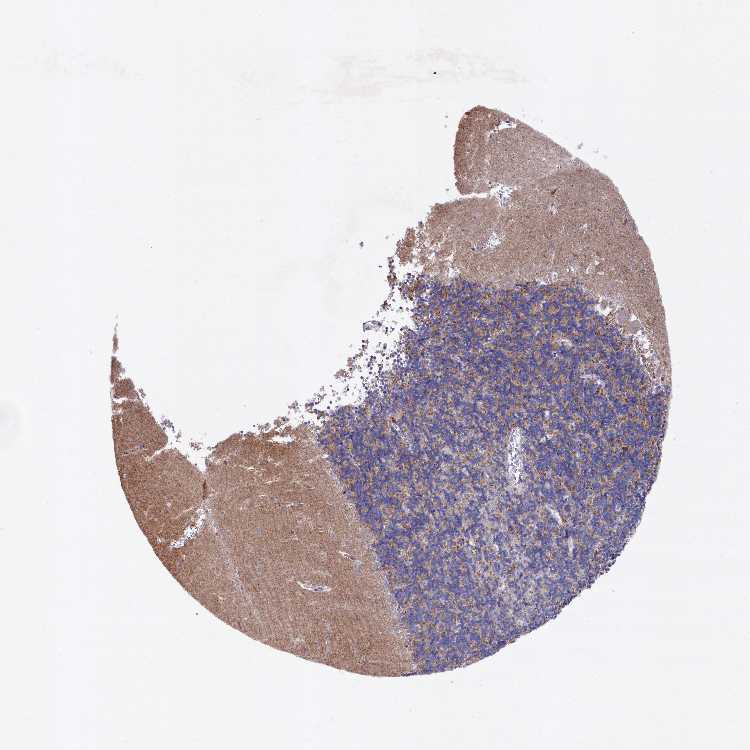

CEREBELLUM - Antibody stainingi

Antibody staining in the annotated cell types in the current human tissue is reported as not detected, low, medium, or high, based on conventional immunohistochemistry profiling in selected tissues. This score is based on the combination of the staining intensity and fraction of stained cells.

Each image is clickable and will lead to virtual microscopy that enables deeper exploration of all samples and also displays staining intensity scores, fraction scores and subcellular localization as well as patient and tissue information for each sample.

Antibody HPA041924Antibody HPA041951

Purkinje cells LowHigh

Cells in granular layer MediumMedium

Cells in molecular layer Not detectedLow